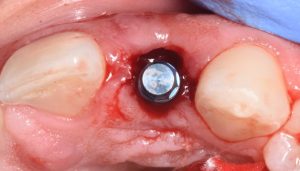

This video demonstrates immediate implant placement in the esthetic zone following atraumatic extraction of a lateral incisor. Emphasis is placed on preserving the hard and soft tissue architecture critical for predictable esthetic outcomes.

The procedure is presented step by step, including minimally traumatic extraction techniques, immediate implant placement, and fabrication and placement of a customized healing abutment to support peri-implant soft tissue contours. Clinical principles for maintaining papillae, controlling the emergence profile, and optimizing soft tissue healing are highlighted.